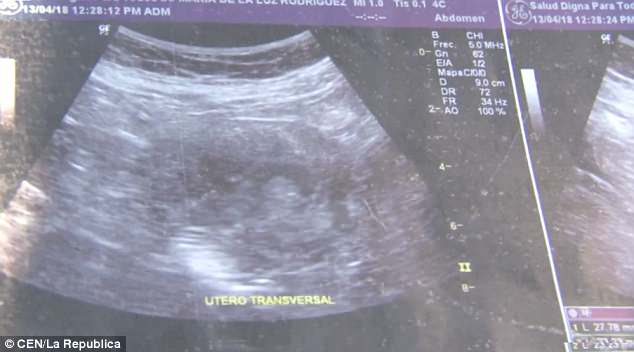

“Le mie gambe mi facevano male, vomitavo e mi sentivo stordita, ora mi hanno fatto 10 ultrasuoni in una clinica privata e in un ospedale pubblico. I medici non riuscivano a crederci” ha dichiarato la donna.